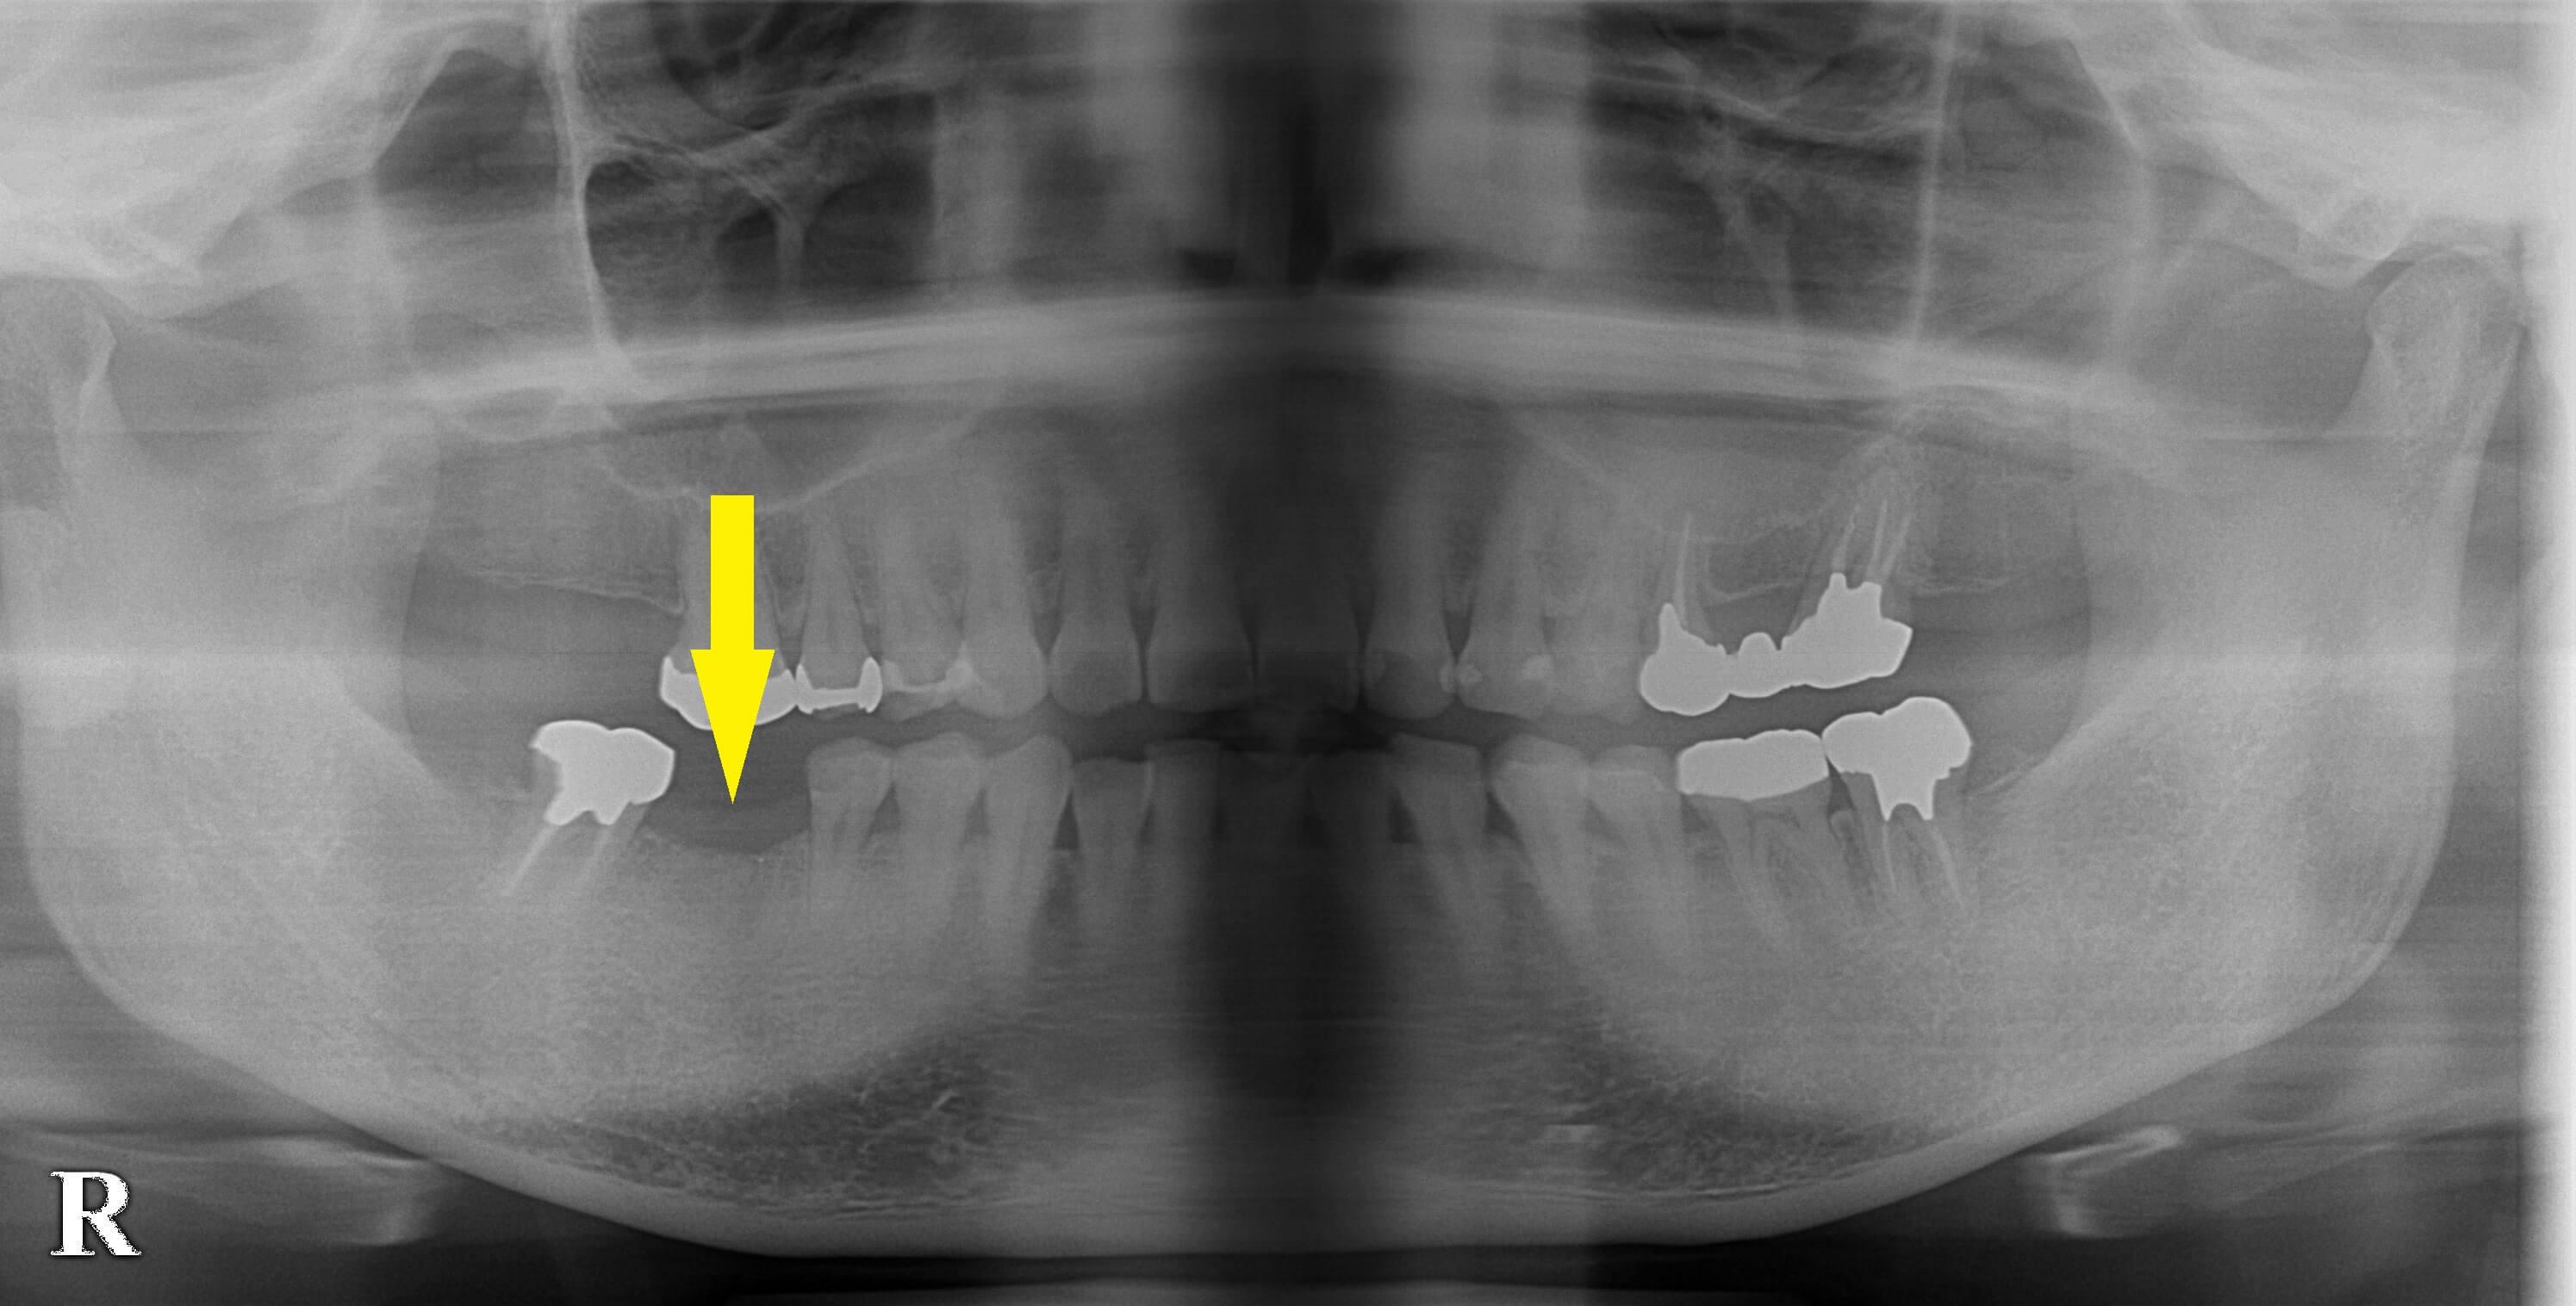

右下顎第一大臼歯を抜歯され、数か月そのままにしていたそうですが、やはり何か治療をした方が良いと考え、いろいろお調べになってインプラント治療をしようと当院に相談にお出でになりました。

レントゲン、CTにて骨量に問題ありませんでしたので、本日インプラント埋入術を施行しました。